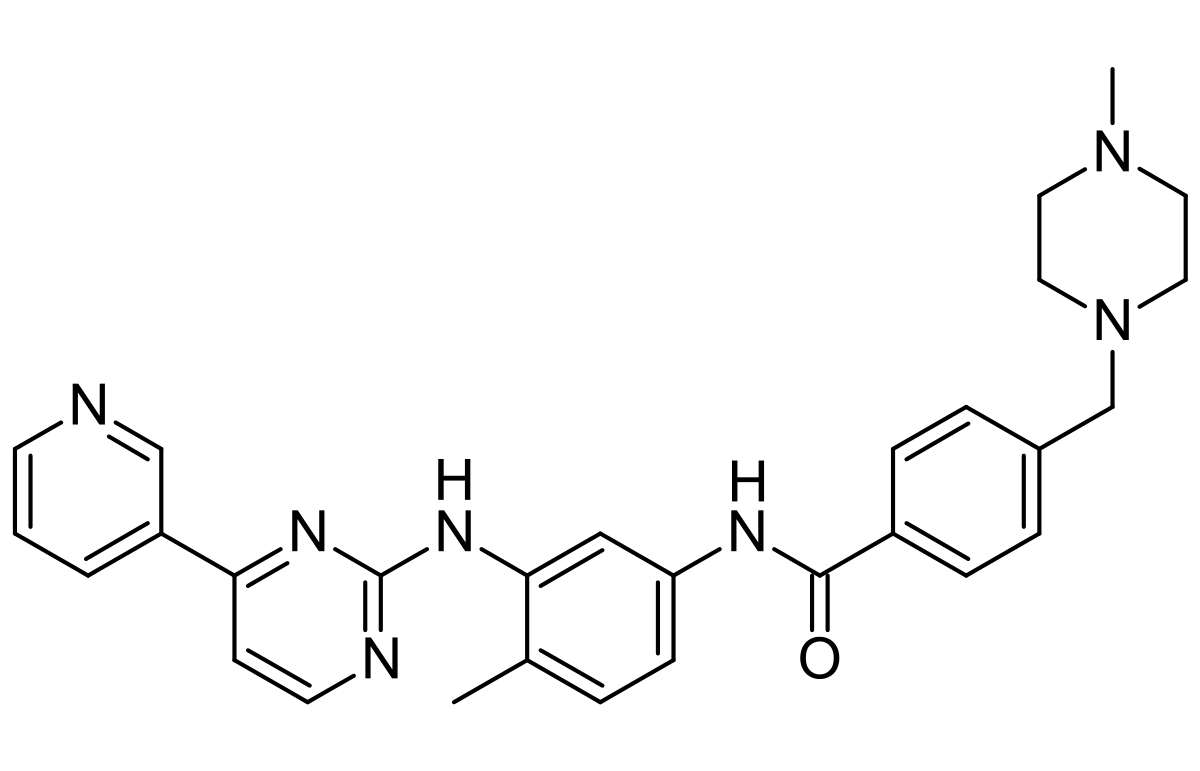

- Leading manufacturer of key anti-cancer APIs.

We continue our focus to bring innovation in Fermentation technologies, Liposomal drug delivery technologies, Lipid based drug delivery technologies, Nanoparticle drug delivery technologies, Synthetic chemistry & High potent cytotoxic products.